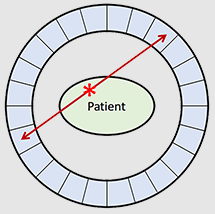

What is the relationship between each detector pair inside the ring of detectors in a PET camera?

Each detector works together with the detector opposite to it – allows it to pick up on a line of response

What is a line of response?

When the photons from an annihilation reaction are emitted, they will travel in opposite directions of one another – makes a 180-degree line almost

How does a ‘dot’ from our image translate from the reaction at the PET detectors?

The detectors create a dot on our scanned image from the point at which the 2 photons are overlapping – or where they cross each other in the ring of detectors but we still need more information to specifically determine it!

What is needed in order for the PET detectors to determine where an annihilation reaction occurred on a line of response?

Requires multiple line of responses to figure out where the intersection of where the annihilation reaction took place

What is a true coincidence?

This is the type of annihilation event that we want to occur – the detectors pick up on the energies emitted from annihilation directly opposite of each other (180°)